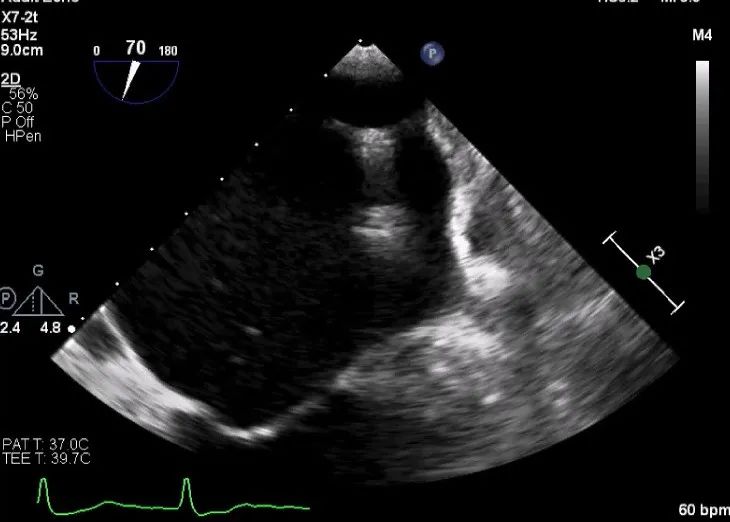

术中超声

确定房间隔穿刺点:靠后

2D视图下测量大鞘长度2cm

3D视图打开夹子

X-plane:下第夹子尝试捕获2区

X-plane:测量前叶长25mm,后叶长14.2mm

X-plane:计算前叶捕获长度8mm,后叶捕获长度7mm

3D视图下观察二尖瓣双孔形态

3D-color:残余少量返流